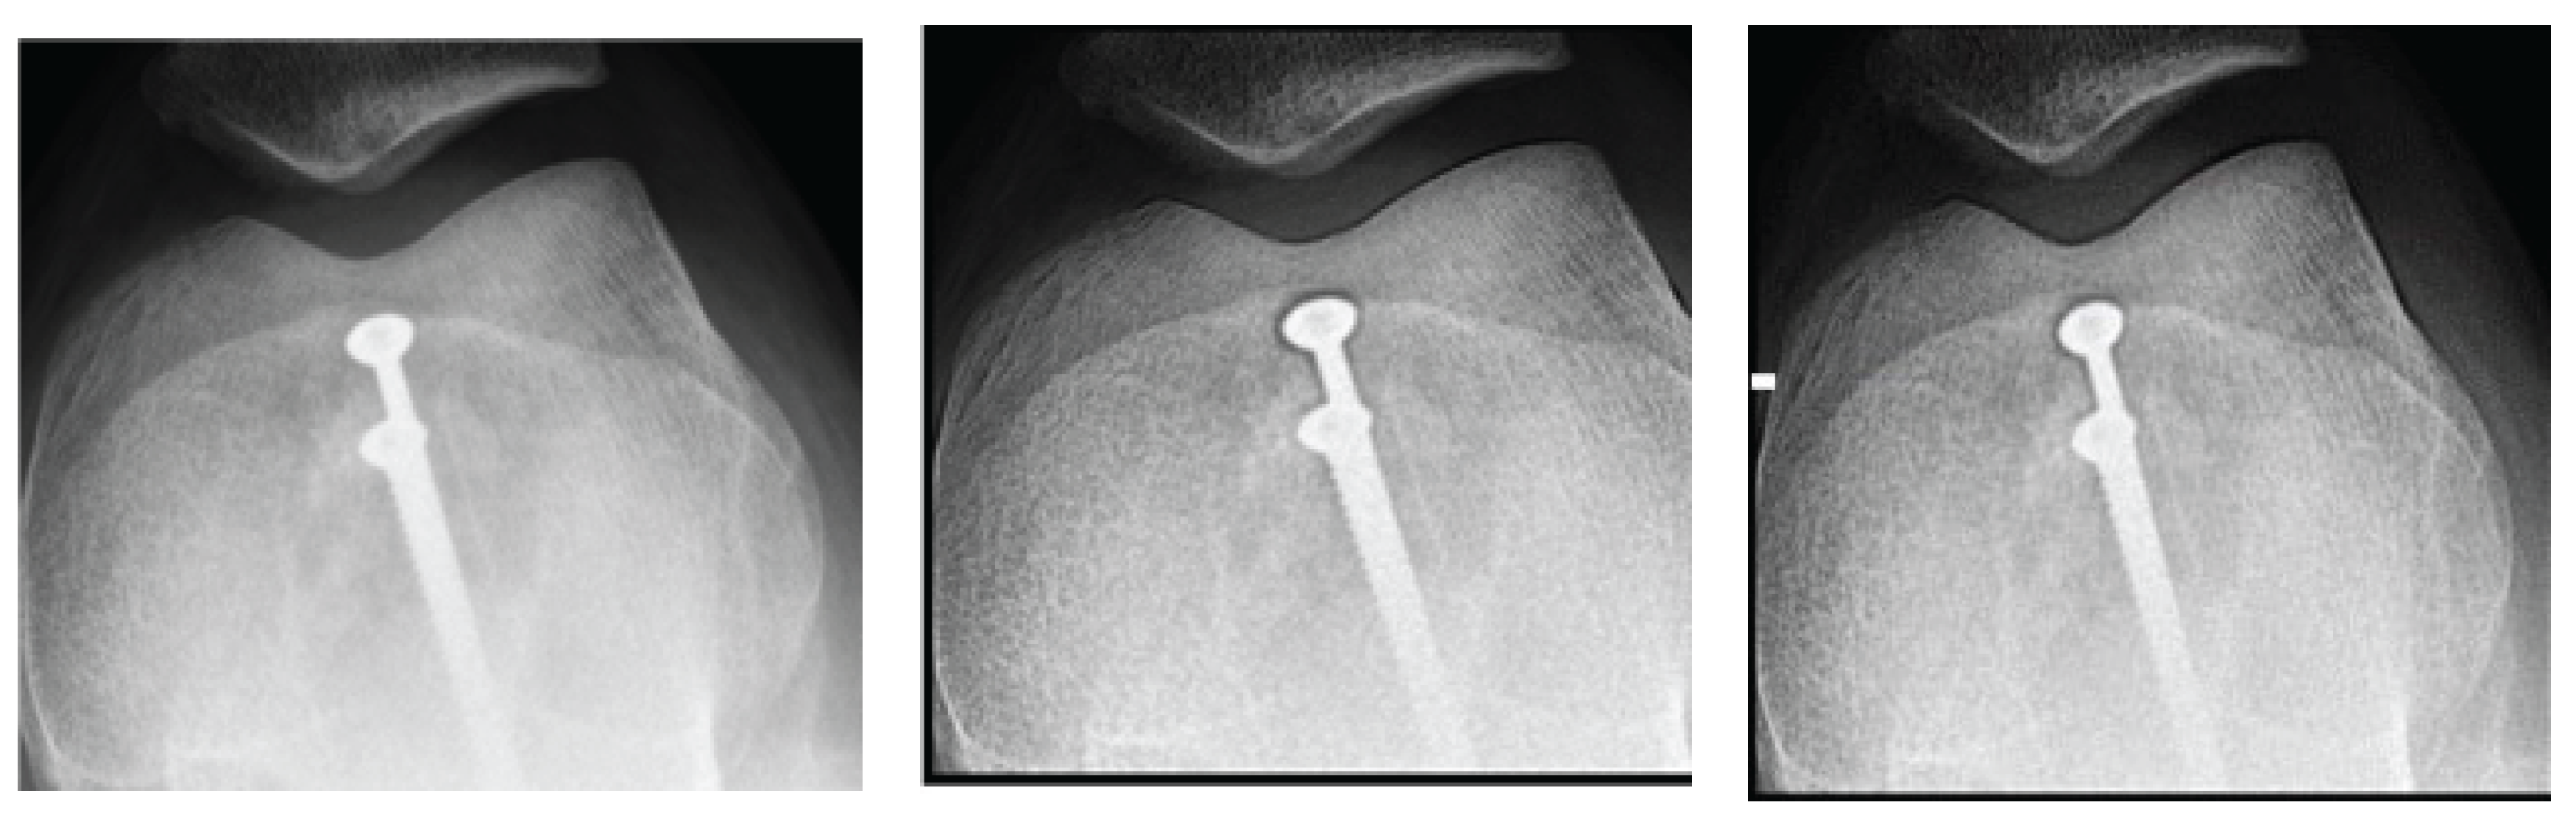

Figure 1 shows the results obtained for the knee image. A significant improvement in contrast and sharpness is observed in the images processed with both filters; Figures 1(b) and 1(c) compared to the original image Figure 1(a). These filters more clearly highlight the details of the bone structures and trabeculae. The contrast increases up to a value of d = 1.4, as seen in Table 1.

Table 1 shows the numerical values of contrast and entropy for different d values in the knee image. It is observed that both filters achieve an increase in contrast, with a change in slope around d = 1.4, indicating image improvement. Entropy also shows a smooth upward trend, indicating that the algorithm does not introduce excessive noise into the image.

For the knee image, an increase in contrast is observed for both filters, with a change point in the slope (Figure 2). Entropy showed a smooth ascending behaviour (Figure 3).

The results obtained demonstrate the effectiveness of the proposed algorithm in improving contrast and sharpness in radiographs, especially in images of the knee (Figure 1) and wrist (Figure 7). Figures 2, 5, and 8 show the contrast behaviour, and Figures 3, 6, and 9 show the entropy as a function of the parameter d for each image type. This implies that the filter reduces the reported scattering effects and tissue heterogeneity. In knee images, where higher energies are used (50 keV or more), Compton and photoelectric effects predominate. In these cases, the proposed filters successfully modelled image degradation due to radiation scatter, which was reflected in a significant improvement in contrast and sharpness.

Figure 1. Knee images (a) original, (b) processed with Cream filter, (c) processed with Bosso filter.